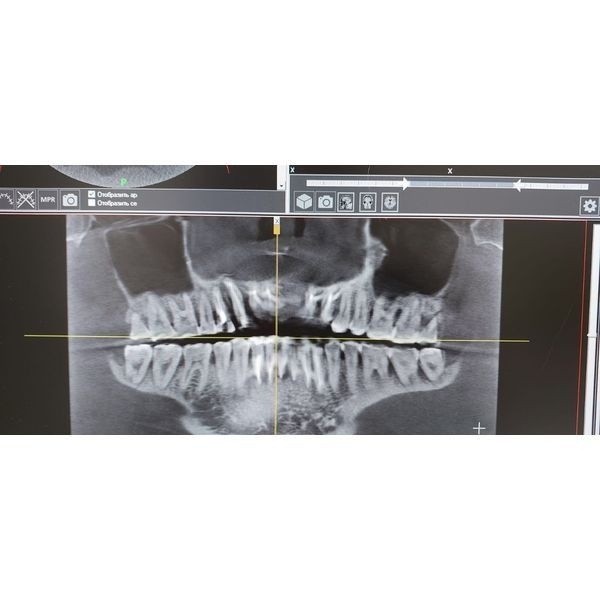

КТ показала:

- истончение межзубных перегородок до половины их длины и более;

- расширение периодонтальных связок зубов;

- гранулёмы в области верхушек зубов 4.1 и 2.7 (верхнего левого моляра);

- пародонтальная киста в области зуба 1.3;

- краевые дефекты (зазубренности) костной ткани из-за истончения зуба 2.1;

- частичная потеря вестибулярной кортикальной пластинки в области отсутствующего зуба 2.1.